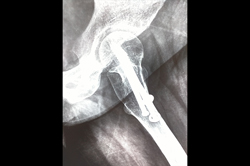

Periprosthetic Fracture THR